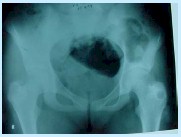

ENFERMEDAD DE OLLIER:

Acortamientos y deformidades. Calcificación moteada. El 25 % hace condrosarcoma. Es múltiple.

Se hace curetaje, relleno y control.. “Todo el hueso está deformado”

Figura 7: enfermedad de Ollier